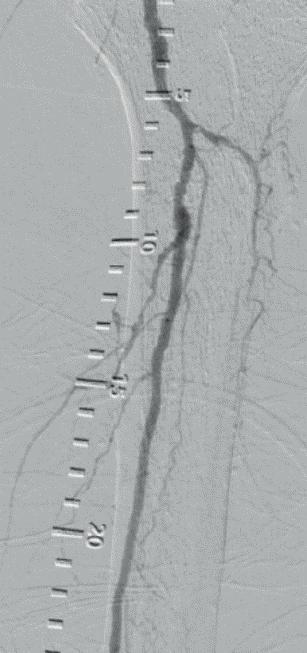

Multicentre experience shows “promising” midterm outcomes with IVL for calcified iliac occlusive disease

Shockwave intravascular lithotripsy (IVL) “expands endovascular strategies for iliac occlusive disease and can facilitate a ‘leave nothing behind’ approach,” Stefano Fazzini (Tor Vergata University, Rome, Italy) and colleagues write in an open-access Journal of Vascular Surgery (JVS) paper highlighting midterm outcomes from the IVLIAC registry—a multicentre, retrospective study of prospectively collected data.

“CALCIUM REMAINS A CHALLENGE IN the endovascular treatment of iliac artery disease, affecting both procedural and long-term outcomes,” Fazzini tells Vascular News. He goes on to comment that the standard approach of primary stenting, “although effective, is susceptible to stent recoil and under expansion in heavily calcified vessels” and notes that extensive calcification increases the risk of ruptures, especially when high-pressure balloons or balloon-expandable stents are used.

Fazzini also stresses that “no single stent is ideal for all calcified iliac lesions,” and that unnecessary stenting, especially at the bifurcation or when covering key branches, “can be avoided”.

In light of this, Fazzini et al set out to evaluate the midterm outcomes of patients with calcified iliac lesions treated with IVL, with or without adjunctive stenting, and to propose a new algorithm guiding these different treatment strategies.

The new algorithm, Fazzini explains, is based on lesion type (stenosis versus chronic total occlusion) and intraoperative functional assessments (extravascular ultrasound and pressure gradient) to determine whether stenting is necessary. “The impact

of sonic pressure waves improves vessel compliance and luminal gain, but such modifications may not always be evident on digital subtraction angiography alone,” he says, adding that intraoperative functional assessments play a “crucial” role in determining whether IVL alone is enough.

The investigators included all consecutive patients at four centres (Rome, Milan, Negrar and Trento) who underwent treatment with the Shockwave Medical peripheral IVL system for calcified iliac arteries from February 2021 to May 2024. Indication for IVL was Rutherford category of three or above in iliac lesions with moderate-to-severe calcification and was based on the new algorithm. The primary endpoint was primary patency, with assisted primary patency, secondary patency, and freedom from iliac complications also analysed.

Fazzini and colleagues share in JVS that a total of 100 iliac arteries were treated in 86 patients. They note that chronic limb-threatening ischaemia (CLTI) was present in 55% of patients, mean target lesion length was 40.95±29.25mm with a mean stenosis of 84±10%, and 12 of the lesions were chronic total occlusions. The authors report that technical

Target lesions were treated with

77%

IVL alone

23% IVL plus adjunctive stenting

success was 99% and that target lesions were treated with IVL alone in 77% of cases, whereas IVL plus adjunctive stenting was employed in the remaining 23% of the cases. They add that provisional stenting was performed in 11% of cases, while planned stenting was performed in 12%, and that mean residual stenosis was 14.95±14% at final angiogram. Primary patency and assisted primary patency at 24 months were 95% and 98%, respectively, while secondary patency was 100%. Primary patency showed no statistically significant difference between the IVL only and IVL plus adjunctive stenting groups.

“Shockwave IVL offers a safe and effective treatment option for calcific iliac occlusive disease,” the authors write in their conclusion. “This multicentre experience shows promising midterm results in terms of primary patency despite the very low stenting rate, preserving future treatment options.” They go on to stress that further studies are needed to confirm these findings.

Discussing the findings with Vascular News, Fazzini summarises that, in cases of severely calcified disease, “Shockwave IVL as a first-line strategy in iliac interventions allows for either the avoidance of unnecessary stenting or optimisation of stent expansion, both of which contribute to favourable midterm outcomes”.